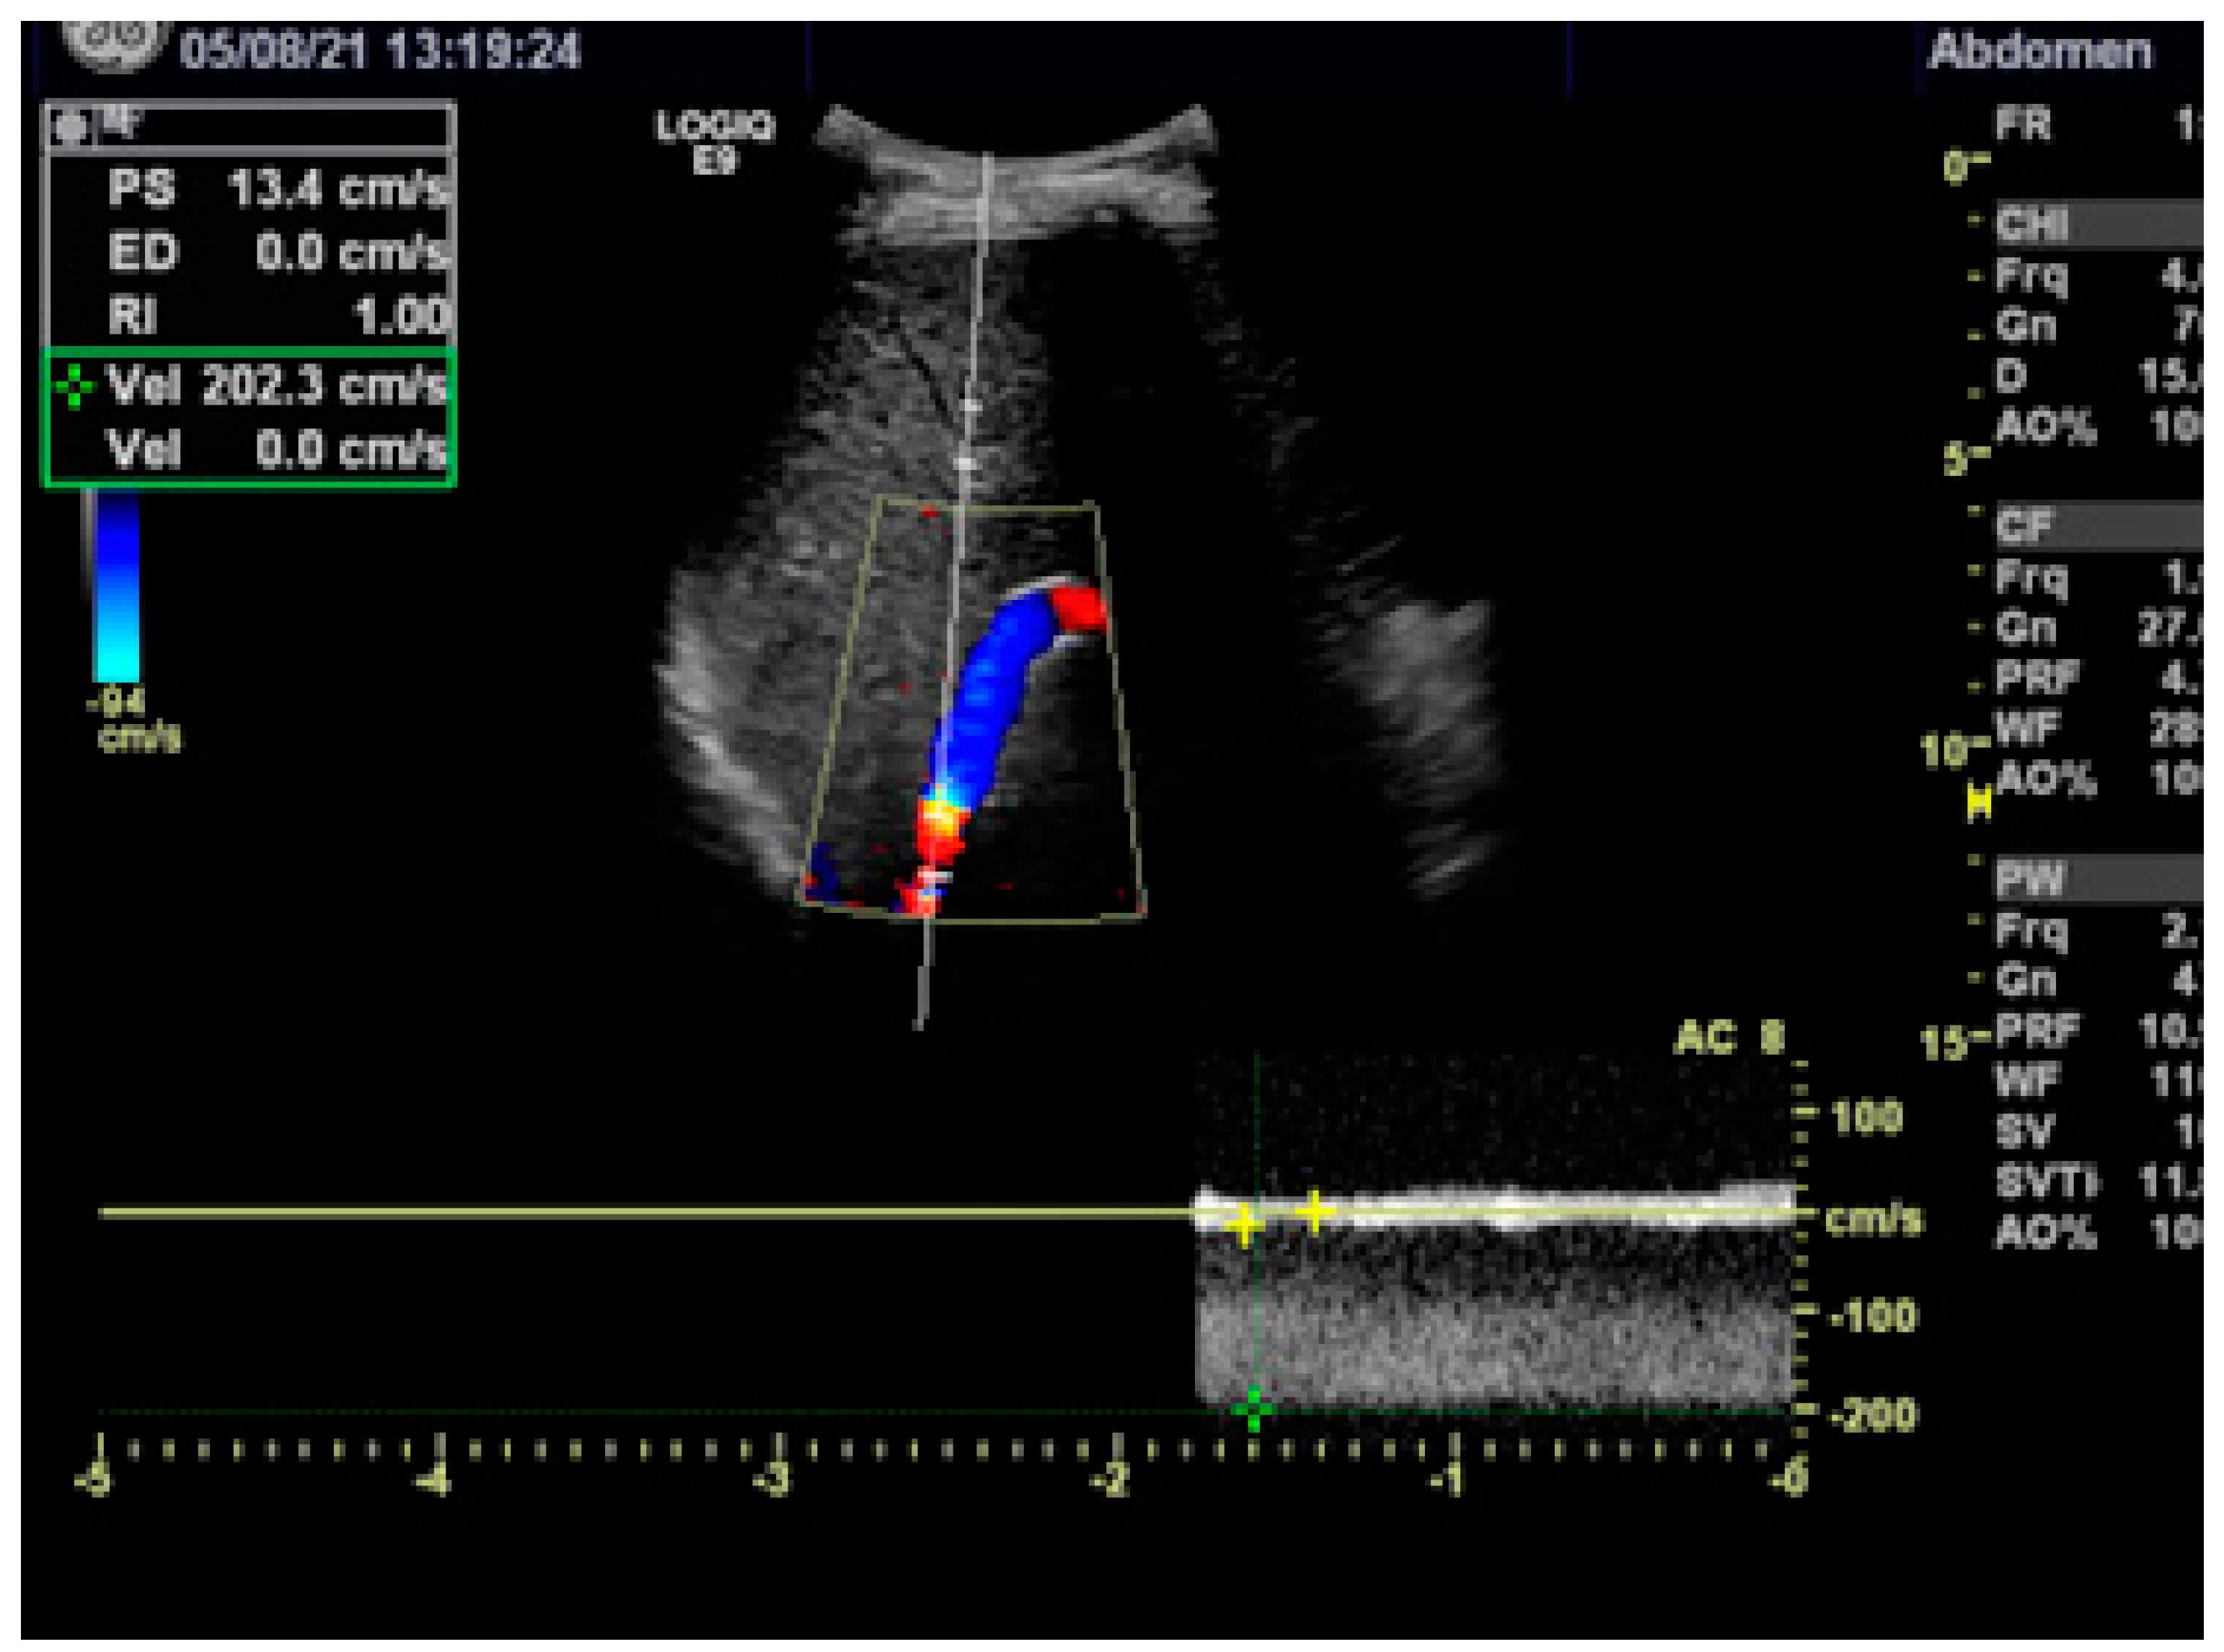

2.3. Pre- and Post-Interventional Management

3.1. Hemodynamics